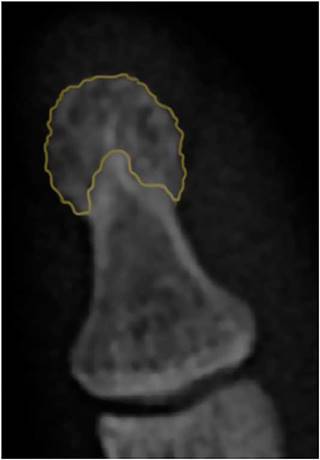

The DPTH does not have a universal radiographic definition, nevertheless, it can be considered as the area of the distal phalanx where the cortical changes from being completely smooth, to acquire a lanceolated appearance8 (Fig. 1). The DPTH is close related with the SEC, therefore, it is a very useful element in the approach of the inflammatory joint diseases (IJD) that can be easily characterized by plain radiography, however, the evidence about the radiographic lesions that compromise it and its performance to establish a differential diagnosis between the IJD is limited.

Fig. 1 Usual radiographic appearance of the tuft. The orange color demarcates the area corresponding to the DPTH. Denote the typical lanceolated appearance (in lobes) of the cortical.